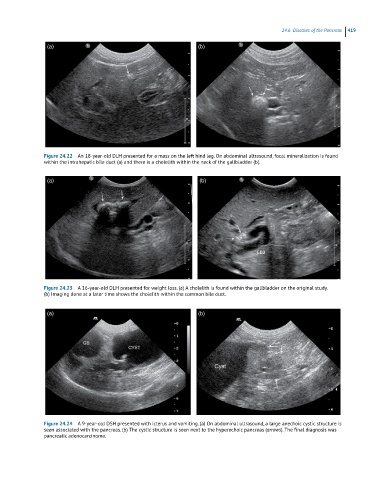

Figure 24.22 An 18-year-old DLH presented for a mass on the left hind leg. On abdominal ultrasound, focal mineralization is found

within the intrahepatic bile duct (a) and there is a cholelith within the neck of the gallbladder (b).

Figure 24.23 A 16-year-old DLH presented for weight loss. (a) A cholelith is found within the gallbladder on the original study.

(b) Imaging done at a later time shows the cholelith within the common bile duct.

Figure 24.24 A 9-year-old DSH presented with icterus and vomiting. (a) On abdominal ultrasound, a large anechoic cystic structure is

seen associated with the pancreas. (b) The cystic structure is seen next to the hyperechoic pancreas (arrows). The final diagnosis was

pancreatic adenocarcinoma.